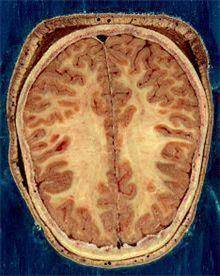

![뇌의 백질과 회색질 [출처: 위키백과]](https://img3.daumcdn.net/thumb/R658x0.q70/?fname=https://t1.daumcdn.net/news/202312/18/yonhap/20231218084824850rhts.jpg)

뇌는 신경 세포체로 구성돼 입력된 정보를 처리하는 겉 부분인 대뇌 피질과 신경세포들을 서로 연결하는 신경 섬유망이 깔려 서로 다른 뇌 부위들을 연결하는 속 부분인 수질로 이루어져 있다. 피질은 회색을 띠고 있어 회색질, 수질은 하얀색을 띠고 있어 백질이라고 불린다.